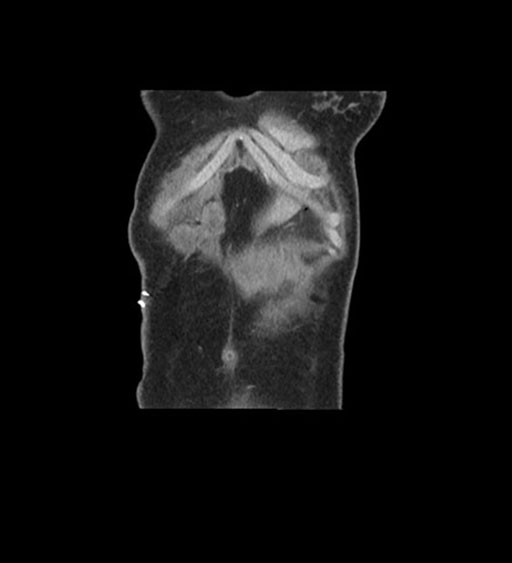

Coronal Arterial

Coronal Venous

Imaging analysis

Based on initial findings, which issue(s) would you be most concerned about?